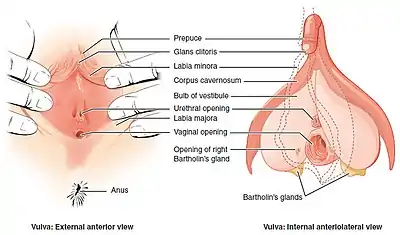

In mammals, the vulva (pl.: vulvas or vulvae) consists of the external female genitalia. The human vulva includes the mons pubis (or mons veneris), labia majora, labia minora, clitoris, vestibular bulbs, vulval vestibule, urinary meatus, the vaginal opening, hymen, and Bartholin's and Skene's vestibular glands. The urinary meatus is also included as it opens into the vulval vestibule. Other features of the vulva include the pudendal cleft, sebaceous glands, the urogenital triangle (anterior part of the perineum), and pubic hair. The vulva includes the entrance to the vagina, which leads to the uterus, and provides a double layer of protection for this by the folds of the outer and inner labia. Pelvic floor muscles support the structures of the vulva. Other muscles of the urogenital triangle also give support.

Structure

The main structures of the vulva are: the mons pubis, the labia – labia majora and labia minora, the external parts of the clitoris – the clitoral hood and the glans, the urinary meatus, the vaginal opening and hymen, and Bartholin's and Skene's vestibular glands.[1] Other features include the pudendal cleft, pubic hair, sebaceous glands, the vulval vestibule, and the urogenital triangle.[2]

The labia majora and the labia minora cover the vulval vestibule.[8] The outer pair of folds, divided by the pudendal cleft, are the labia majora (Neo-Latin for "larger lips"). They contain and protect the other structures of the vulva.[8] The labia majora meet at the front at the mons pubis, and meet posteriorly at the urogenital triangle (the anterior part of the perineum) between the pudendal cleft and the anus.[9][6] The labia minora are often pink or brownish black, relevant to the person's skin color.[10]

The grooves between the labia majora and labia minora are called the interlabial sulci, or interlabial folds.[11] The labia minora (smaller lips) are the inner two soft folds, within the labia majora. They have more color than the labia majora[3] and contain numerous sebaceous glands.[12] They meet posteriorly at the frenulum of the labia minora, a fold of restrictive tissue. The labia minora meet again at the front of the vulva to form the clitoral hood, also known as the prepuce.[13]

The visible portion of the clitoris is the clitoral glans. Typically, this is roughly the size and shape of a pea, and can vary in size from about 6 mm to 25 mm.[13] The size can also vary when it is erect.[6] The clitoral glans contains as many nerve endings as the much larger homologous glans penis in the male, which makes it highly sensitive.[13] The only known function of the clitoris is to focus sexual feelings.[13] The clitoral hood is a protective fold of skin which varies in shape and size, and it may partially or completely cover the clitoris.[14] The clitoris is the homologue of the penis,[8] and the clitoral hood is the female equivalent of the male foreskin,[14] and may be partially or completely hidden within the pudendal cleft.[15]

Vestibule

The area between the labia minora where the vaginal opening and the urinary meatus are located is called the vulval vestibule, or vestibule of the vagina. The urinary meatus is below the clitoris and just in front of the vaginal opening which is near to the perineum. The term introitus is more technically correct than "opening", since the vagina is usually collapsed, with the opening closed. The introitus is sometimes partly covered by a membrane called the hymen. The hymen will usually rupture during the first episode of vigorous sex, and the blood produced by this rupture has been seen to signify virginity. However, the hymen may also rupture spontaneously during exercise or be stretched by normal activities such as the use of tampons and menstrual cups, or be so minor as to be unnoticeable, or be absent.[13] In some rare cases, the hymen may completely cover the vaginal opening, requiring a surgical procedure called a hymenotomy.[16] On either side of the back part of the vaginal opening are the two greater vestibular glands known as Bartholin's glands. These glands secrete mucus and a vaginal and vulval lubricant.[17] They are homologous to the bulbourethral glands in the male.[2] The lesser vestibular glands known as Skene's glands, are found on the anterior wall of the vagina. They are homologues of the male prostate gland and are also referred to as the female prostate.[18]